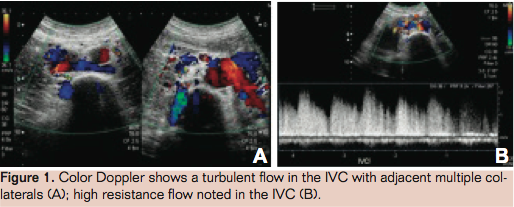

On examination the patient had typical features of inferior vena cave (IVC) syndrome with pitting edema and abdominal wall veins. A Doppler study showed a dilated IVC with a nonvisualized infrahepatic segment above the renal vein drainage and adjacent multiple collaterals (Figure 1). There was severe segmental narrowing of the suprarenal–infrahepatic segment of IVC on contrast enhanced computed tomography (CT) scan (Figure 2). The CT done prior to nephrectomy had shown a patent IVC (Figure 3).